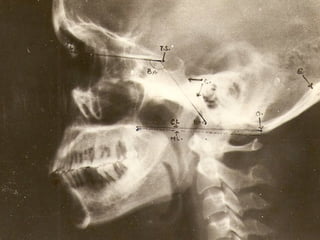

CRANIOMETRY:

Craniometry of the CVJ uses a series of lines, planes

& angles to define the normal anatomic relationships

of the CVJ.

These measurements can be taken on plain X rays,

3D CT or on MRI.